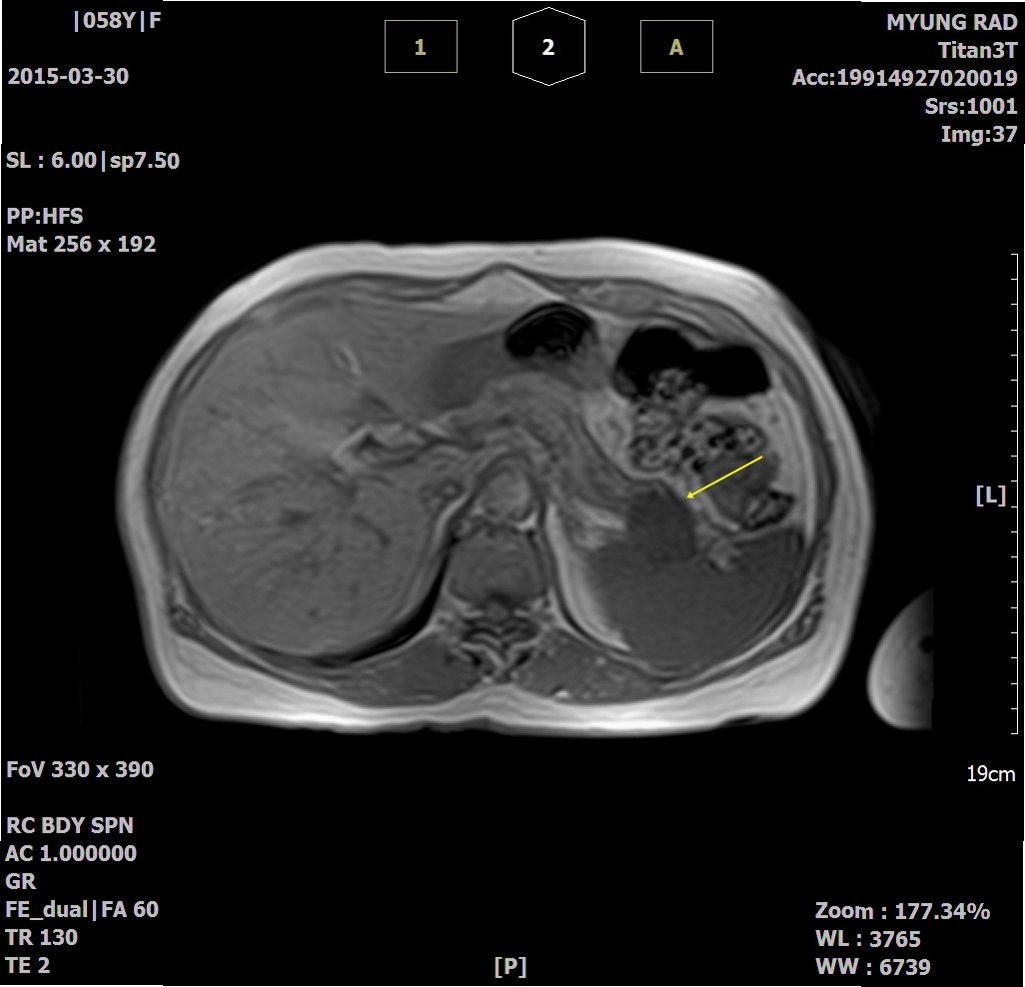

췌장암 진단은 여러 단계를 거쳐 이루어집니다. 췌장암이 의심되는 경우, 먼저 신체 검진과 병력 청취를 통해 전반적인 건강 상태를 평가합니다. 이후, 다양한 영상 검사를 통해 췌장의 상태를 확인합니다. 가장 일반적으로 사용되는 영상 검사에는 복부 CT, MRI, 초음파 검사가 있습니다. 이러한 검사들을 통해 췌장의 종양 유무, 크기, 위치 등을 파악할 수 있습니다.

2. MRI (자기 공명 영상): CT보다 더욱 선명한 영상을 제공하여 작은 종양이나 주변 조직 침범 여부를 확인하는 데 도움을 줍니다.